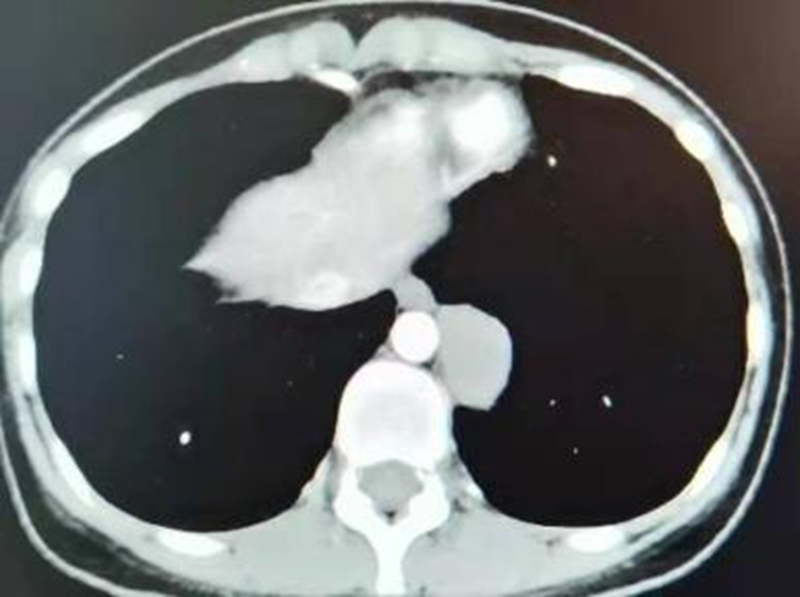

术前

经检查后发现,该患者肿瘤位于后纵隔脊柱旁,大小约5cm×4cm×3cm,与胸主动脉、食管及脊柱关系密切。为了给这位年轻的患者制定更加科学、优质、个性化的治疗方案,科室立即组织专家进行讨论,考虑后纵隔肿瘤可行胸腔镜手术切除,且术后可免行胸腔闭式引流术;6月18号行经单孔胸腔镜下行纵隔肿瘤切除术,术中无出血,术后胸腔免留置胸腔引流管,术后当天患者即下床活动,仅有切口轻微疼痛;术后第2天切口无明显疼痛,康复出院。